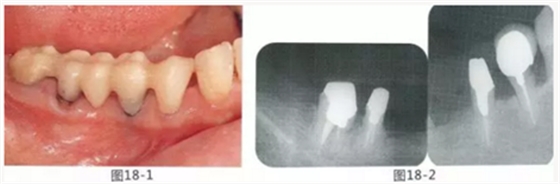

58歲女性,在修復(fù)治療前,為了去除牙周袋和獲得附著齦,頰側(cè)進(jìn)行APF(齦瓣根尖側(cè)轉(zhuǎn)移),FGG(游離齦移植),舌側(cè)進(jìn)行APF(齦瓣根尖側(cè)轉(zhuǎn)移)進(jìn)行對(duì)應(yīng)的病例

圖18-1 右上4,5,6,6,7部位,初期治療結(jié)束時(shí)牙齦的狀態(tài)。

圖18-2 手術(shù)前同部位的口腔X光片。

圖18-4 去除臨時(shí)修復(fù)體后的頰側(cè)面照。在手術(shù)前去除右下5,6,7的金屬樁可以使手術(shù)更為方便。右下5,6部位基本看不到角化牙齦。

圖18-5 同部位的舌側(cè)面照片。角化牙齦較少,將牙槽嵴頂預(yù)測(cè)切開(kāi)的話很有可能會(huì)沒(méi)有任何角化牙齦。